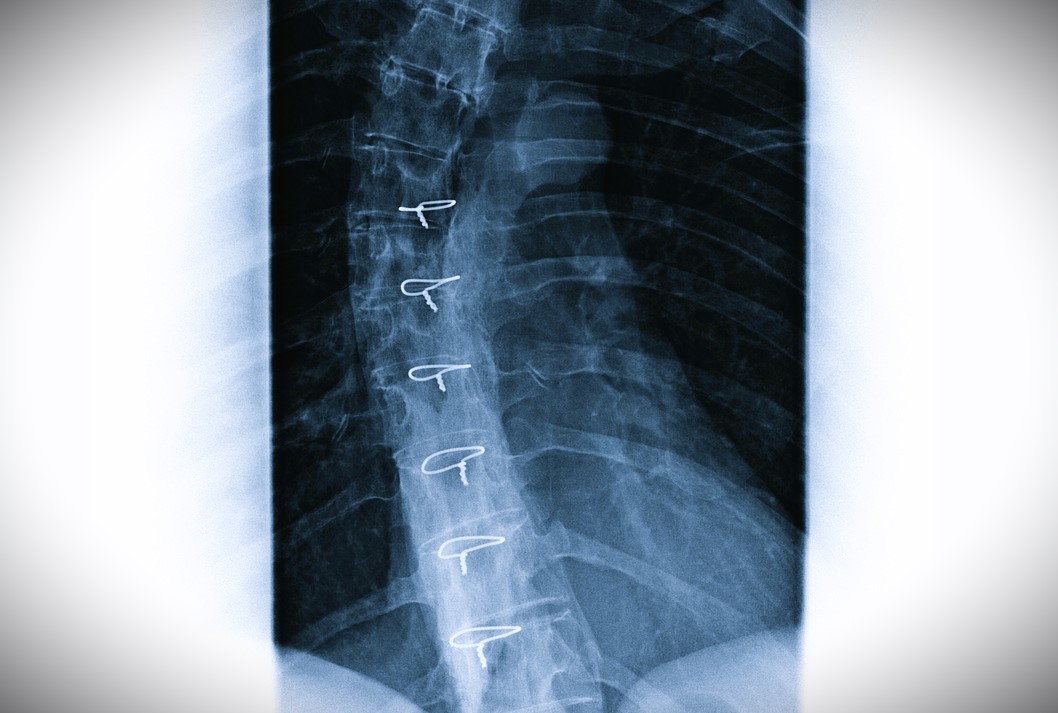

Χανιά – Οι απίστευτες εικόνες με το κόκκαλο από κουνέλι